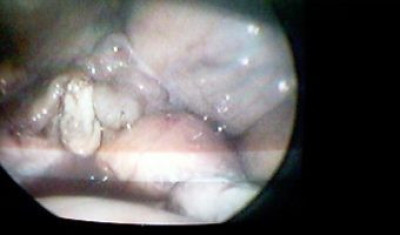

Vesícula atrófica